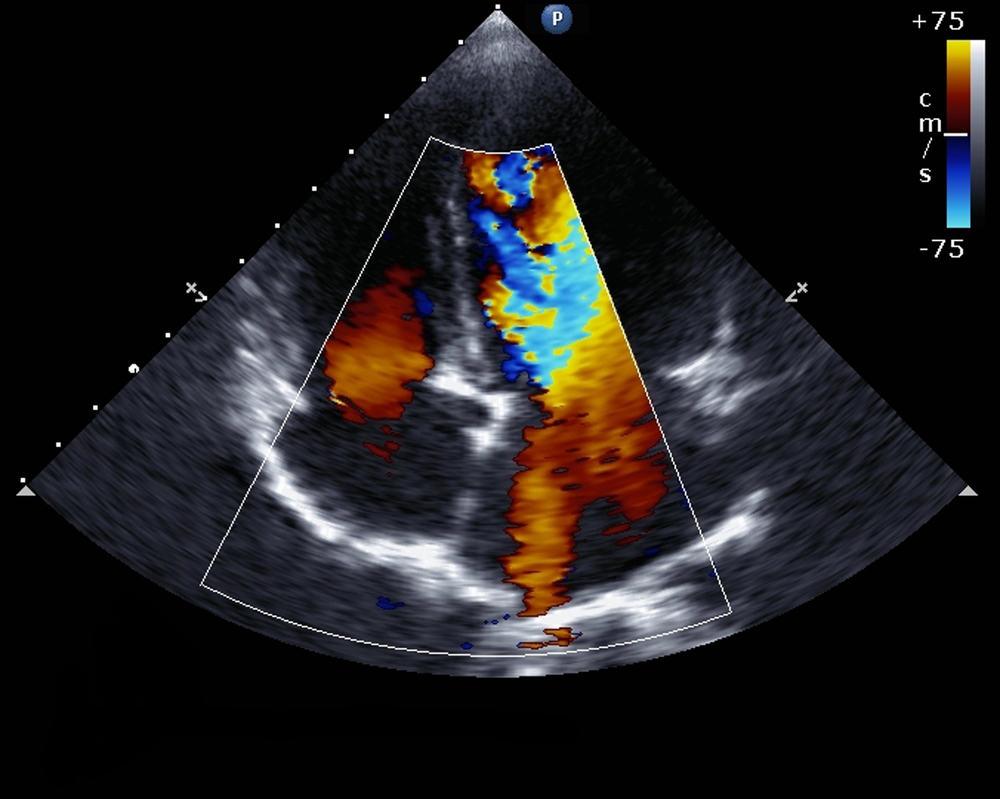

- Siêu âm tim. Đây là xét nghiệm chính được sử dụng để chẩn đoán hở van ba lá. Siêu âm tim sử dụng sóng âm thanh để tạo ra hình ảnh chi tiết của trái tim đang đập. Xét nghiệm có thể cho biết cấu trúc của tim và van tim, bao gồm van ba lá, và dòng chảy của máu qua các vùng tim.